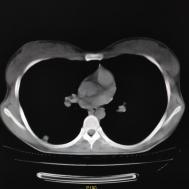

性别:女,年龄:26岁,低热,轻微胸痛,支原体阳性

[影像描述]

两肺内及胸膜下多发斑片状高密度影,部分病灶密度较淡,部分实变,边缘可见渗出改变。